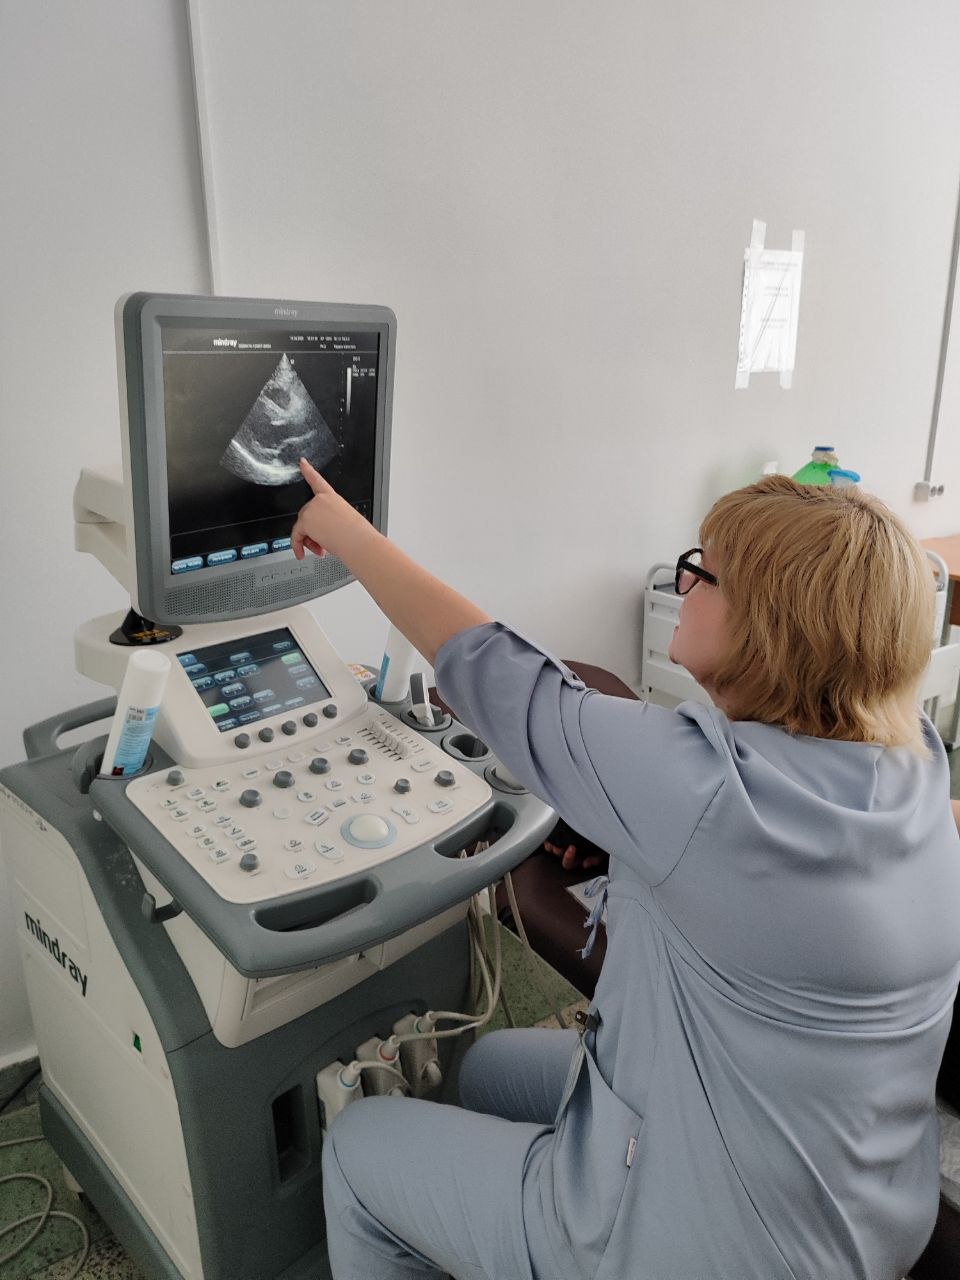

Главный сюрприз ждал ребят во время практической части. Наталья Борисовна и Кирилл организовали для группы экскурсию в кабинет РКТ (рентгеновской компьютерной томографии), а затем переключили внимание на ультразвуковые методы исследования. Под чутким руководством студента-дублёра и Натальи Борисовны каждый участник занятия получил уникальную возможность попробовать себя в роли врача ультразвуковой диагностики. Ребята освоили базовые протоколы сканирования: щитовидной железы, слюнных желез, почек и печени.

Настоящим подарком для студентов стал мастер-класс по эхокардиографии от Натальи Борисовны Кривелевич, которая продемонстрировала тонкости исследования сердца.